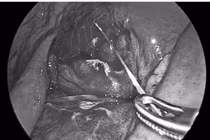

di-vat.jpg

Dị vật được lấy ra - Ảnh BVCC

Ê-kíp phẫu thuật khoa Răng Hàm Mặt do BSCKII Bùi Công Tuấn, Phó khoa Răng Hàm Mặt đã tiến hành phẫu thuật, lấy thành công dị vật là đầu vỏ bút bi kèm lò xo ra khỏi cơ thể người bệnh, đảm bảo an toàn, hạn chế tối đa tổn thương các cấu trúc lân cận. Sau phẫu thuật, bệnh nhân ổn định, giảm đau rõ rệt và đang được tiếp tục theo dõi.